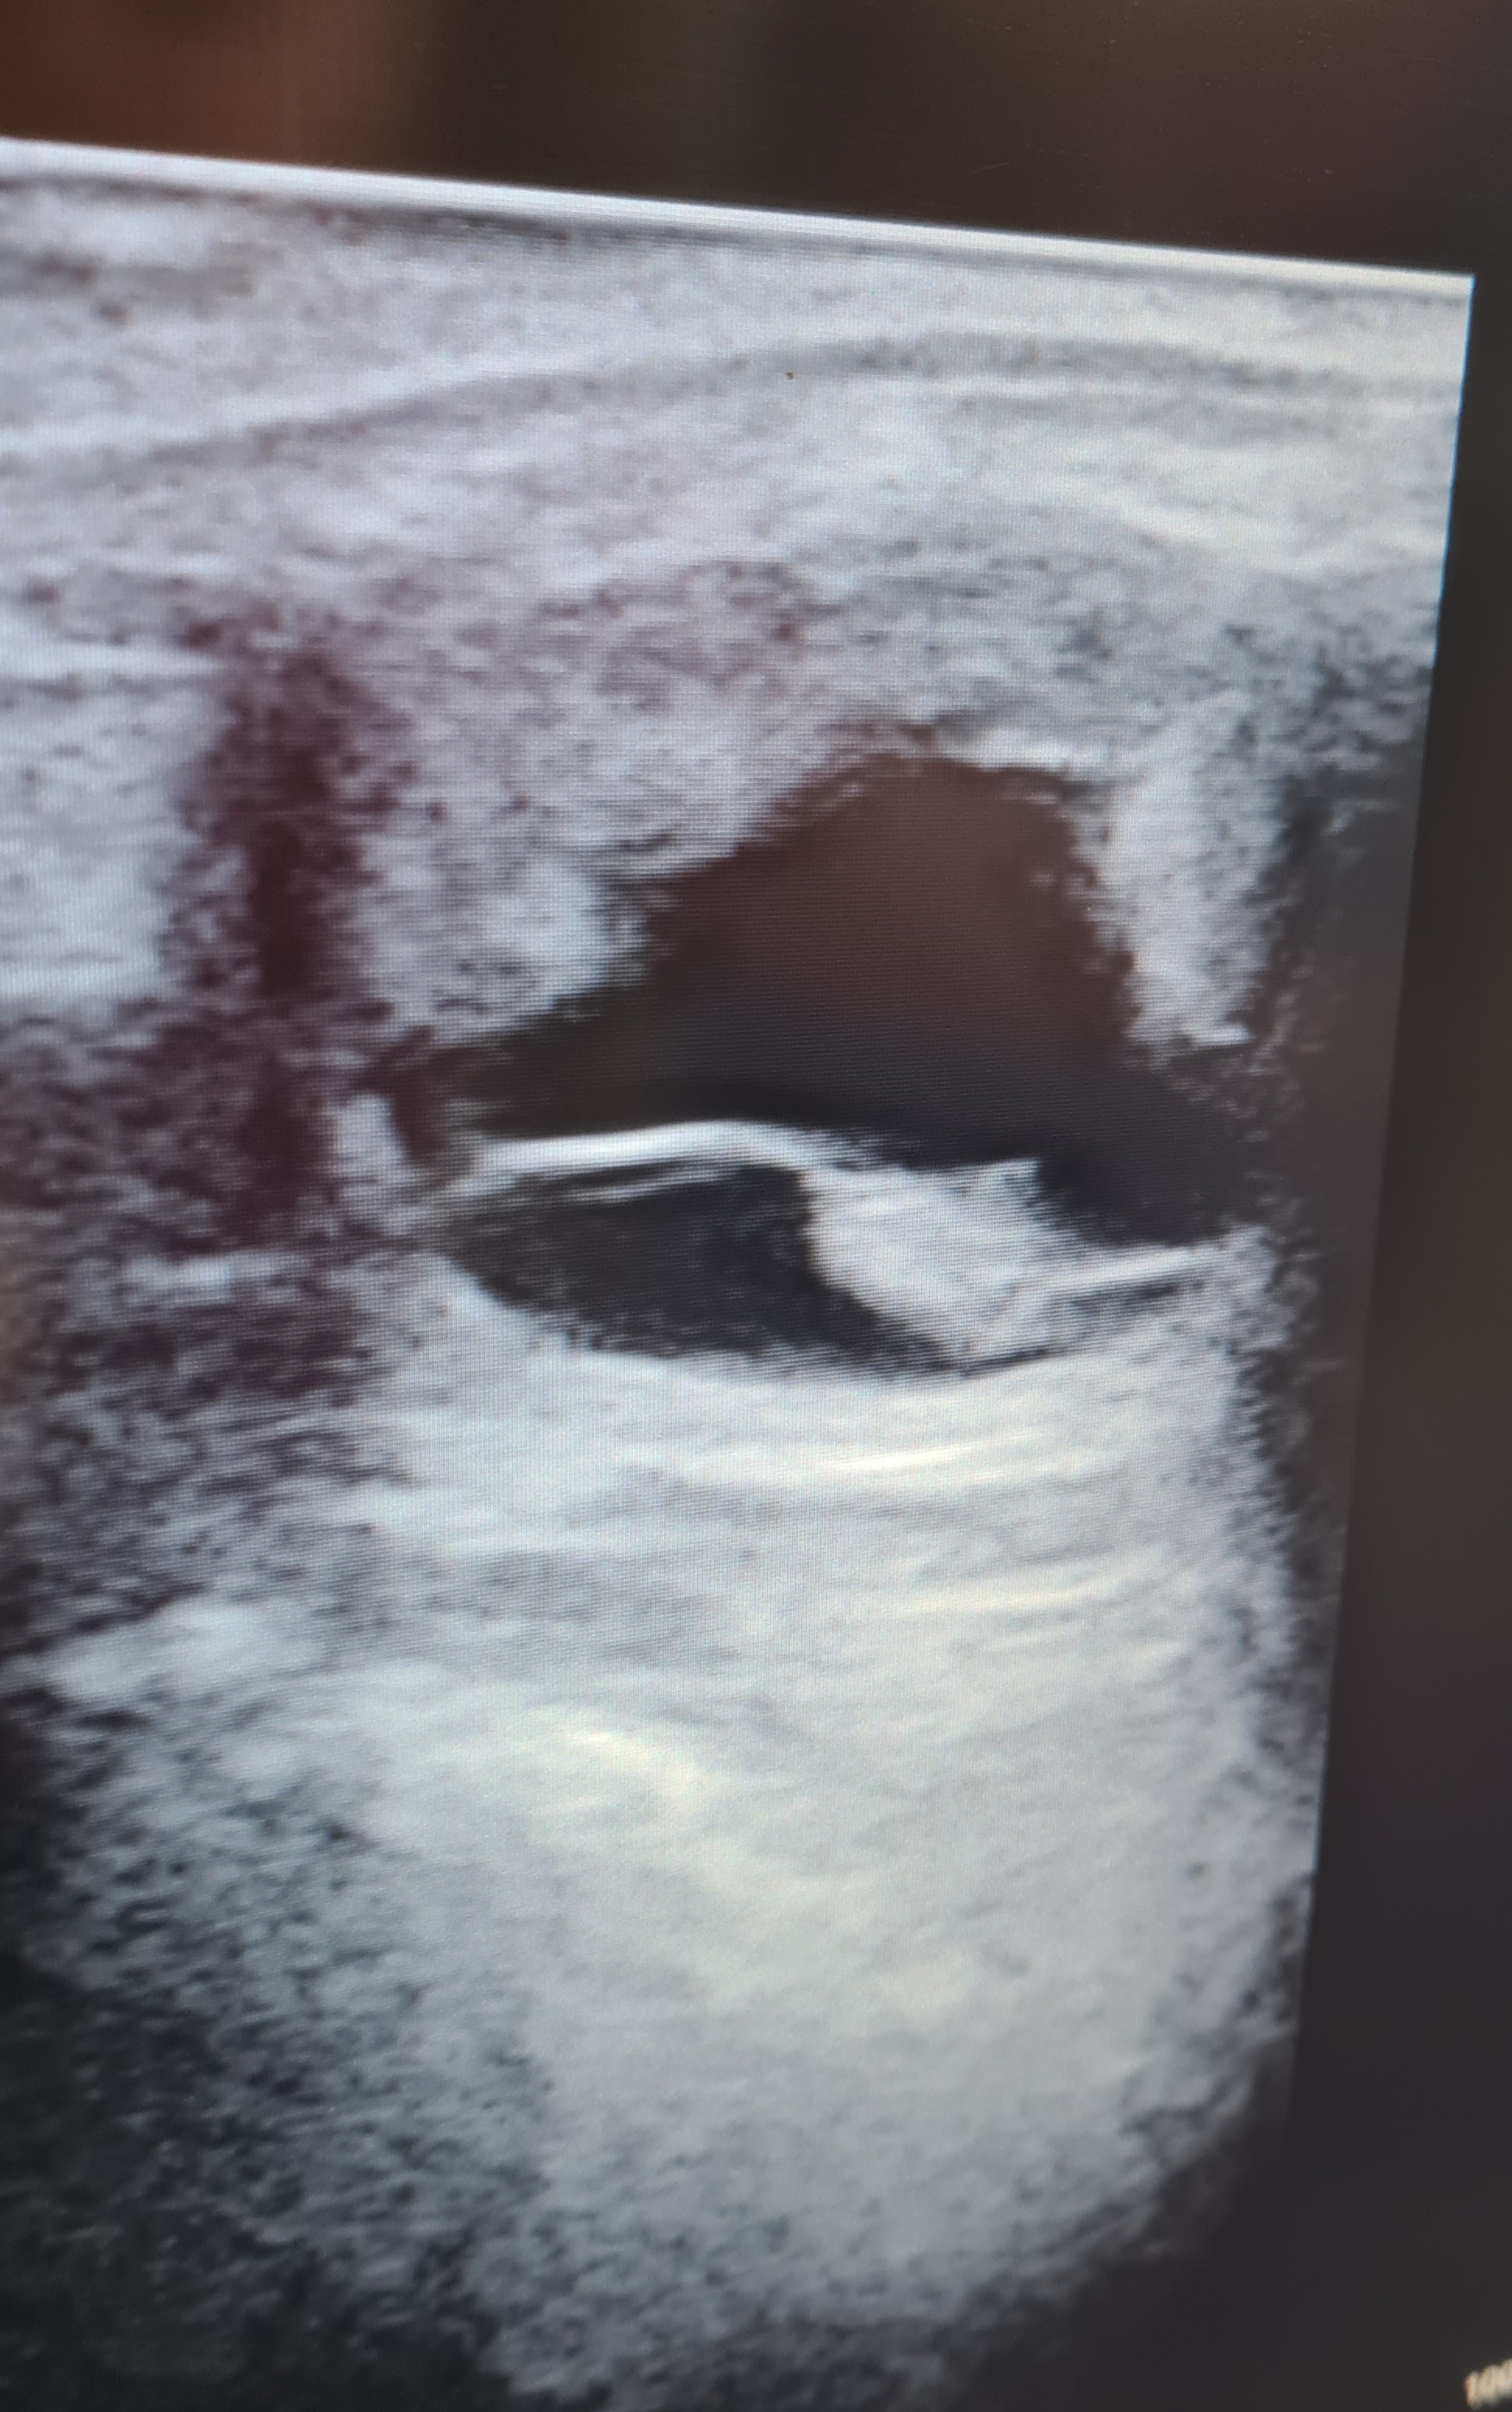

échographie réalisée 28 jours post-ovulation.